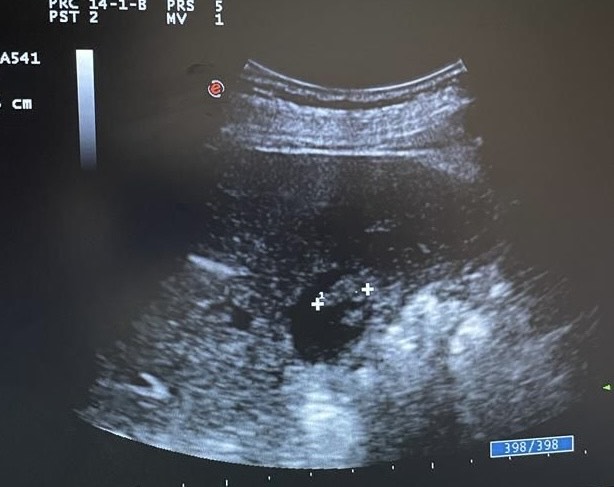

Por primera vez en 23 años de consulta miré las imágenes ecográficas. Y me asaltó la duda, ¿colelitiasis?

Mentalmente describí las lesiones, se trata de lesiones múltiples hiperecogénicas y adheridas a la pared vesicular y que no producen sombra posterior.

Repetí la ecografía para confirmar o descartar mi sospecha.

Confirmé que no se trataba de colelitiasis sino que en mi opinión eran múltiples pólipos vesiculares y alguno de ellos cercano a 1 cm de diámetro, sin poder descartar malignidad con la ecografía, por lo que solicité un TC abdominal que informó de un único pólipo vesicular de 6 mm.

Desde la consulta de cirugía se solicitó ecografía reglada y control en 6 meses que informó de múltiples engrosamientos nodulares en relación con pólipos (más de 10), los de mayor tamaño alcanzan 9 mm de grosor máximo. Alitiasica.